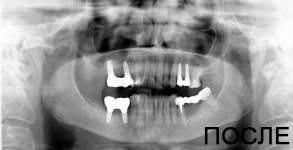

4 работы в портфолио

Удаления зубов любой сложности. Пародонтология (закрытый, открытый кюретаж, лоскутные операции, рецекция верхушки корня, вестибулопластика, френулотомия, френулоэктомия). Переостотомия, вскрытие абсцессов и других воспалительных процессов. Цистотомия, цистэктомия. Имплантология (установка имплантатов различных систем с осложненными анатомическими условиями, направленная костная регенерация, открытый синус-лифтинг, закрытый синус-лифтинг, пластика альвеолярного гребня).

Акопян Антон Владимирович: портфолио (4)